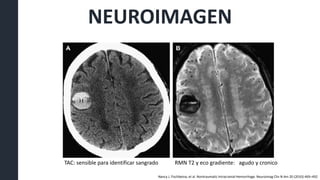

TAC: sensible para identificar sangrado RMN T2 y eco gradiente: agudo y cronico

Nancy J. Fischbeina, et al. Nontraumatic Intracranial Hemorrhage. Neuroimag Clin N Am 20 (2010) 469–492